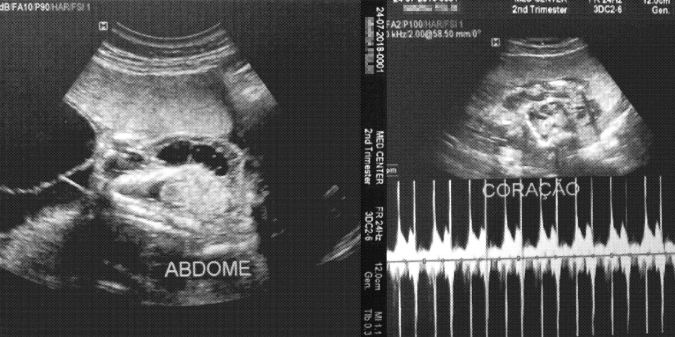

O FILHO DE MARIA Félix, de 21 anos, resistiu pouco mais de seis meses de gestação. Morreu ainda no ventre, com apenas 322 gramas. A causa do aborto, que aconteceu com 25 semanas de gravidez, foi má formação: o bebê tinha o intestino para fora do abdômen e também problemas no coração. Não é incomum que as mães da região percam seus filhos precocemente. O bebê de Maria, ao que tudo indica, foi mais uma vítima precoce do agrotóxico glifosato, usado em grandes plantações de soja e de milho em Uruçuí, a 459 km de Teresina, no Piauí.

Laudo do ultrassom que constatou a morte do bebê. ‘A principal consequência é a atrofia de alguns órgãos’, diz o médico.Imagem: Reprodução

Na maternidade de Floriano, o coordenador do setor de obstetrícia Luiz Rosendo Alves da Silva já viu muitos casos de aborto e de má-formação. Ele acredita na culpa dos agrotóxicos. “É uma contaminação lenta, gradual e diária. A principal consequência é a atrofia de alguns órgãos, principalmente coração e pulmão”.

Foto em destaque: ultrassom que constatou a má-formação no filho de Maria Félix. Ele morreu ainda no útero, com 25 semanas, por causa de má-formação no abdômen e no coração.